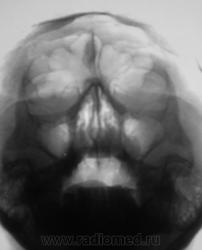

В любом случае опасности представлять не должно. В гайморовых старые фибринозные наслоения и киста

Томограммы.

Может что-то из прошлого, но на патологическое обызвествление "не тянет". Но возможно кто то из КТ - шников что толковое подскажет...

Конечно, серп. К эндокринологу бы её...

Вы считаете, что это локальное обызвествление фалькс церебри?

Ну да, по-моему похоже

А мне, вот, что-то кажется, что имеет место, разница в величине орбит...